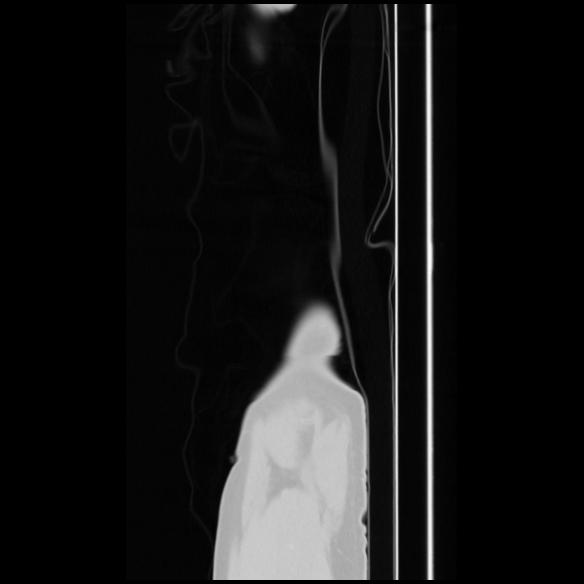

7 CUERPO,CE,Sagittal,3.000,CUERPO,Sagittal,